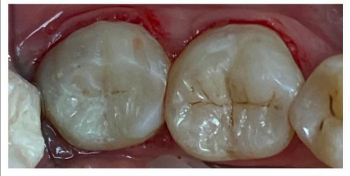

Равиля Равилевна: «Ваша улыбка – показатель здоровья и благополучия. Не даром говорят глаза – зеркало души, а зубы – зеркало здоровья. Цель моей работы – здоровые и красивые зубы пациента. А лучшая награда, когда пациент и окружающие его люди не могут отличить леченый мною зуб от родного здорового!»